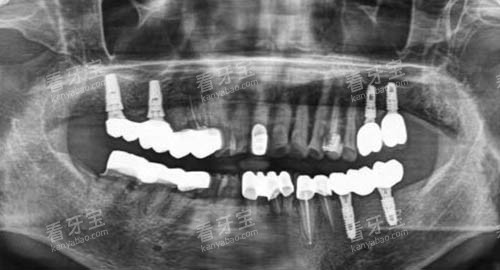

如智能化口腔全景机、口腔CT、激光治疗仪等。

比如,智能化口腔全景机可以快速、清晰地拍摄口腔全景影像,让医生齐全了解患者的口腔结构;口腔CT则能够提供三维立体的口腔图像,为种植牙等复杂手术提供更好的术前规划。